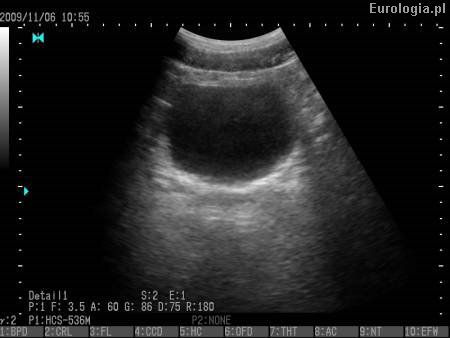

PVR jest skrótem od angielskiego okreslenia Post Void Residual oznaczającego objętość moczu zalegającą w pęcherzu moczowym. PVR jest standardowo używanym skrótem w diagnostyce ultrasonograficznej układu moczowego. Zaleganie moczu w pęcherzu może być przyczyną nwaracjących infekcji układu moczowego.

Fot. Zaleganie moczu w pęcherzu moczowym - PVR 80 ml.